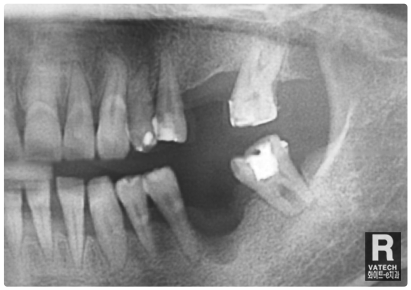

:: 엑스레이 촬영을 통하여 살펴보는 뼈이식 & 임플란트 ::

공간 확보를 위한 엑스레이 촬영

이렇게 임플란트 인공치아 뿌리를 식립하려 하는 자리에

엑스레이 촬영을 통해 공간을 먼저 봅니다.

임플란트 의사 결정

원래라면 저런 어금니 두개가 들어가 있던 자리였죠.

하지만 없으니 임플란트 궈궈!

잇몸뼈 소실 복구

자~ 눈금으로 쉽게 표기해 드릴게요.

보시다시피 옆자리의 잇몸뼈의 높이보다 상당히 내려가

있습니다. 치아가 자리에 없는 동안 많은 잇몸뼈 소실이

원인입니다.